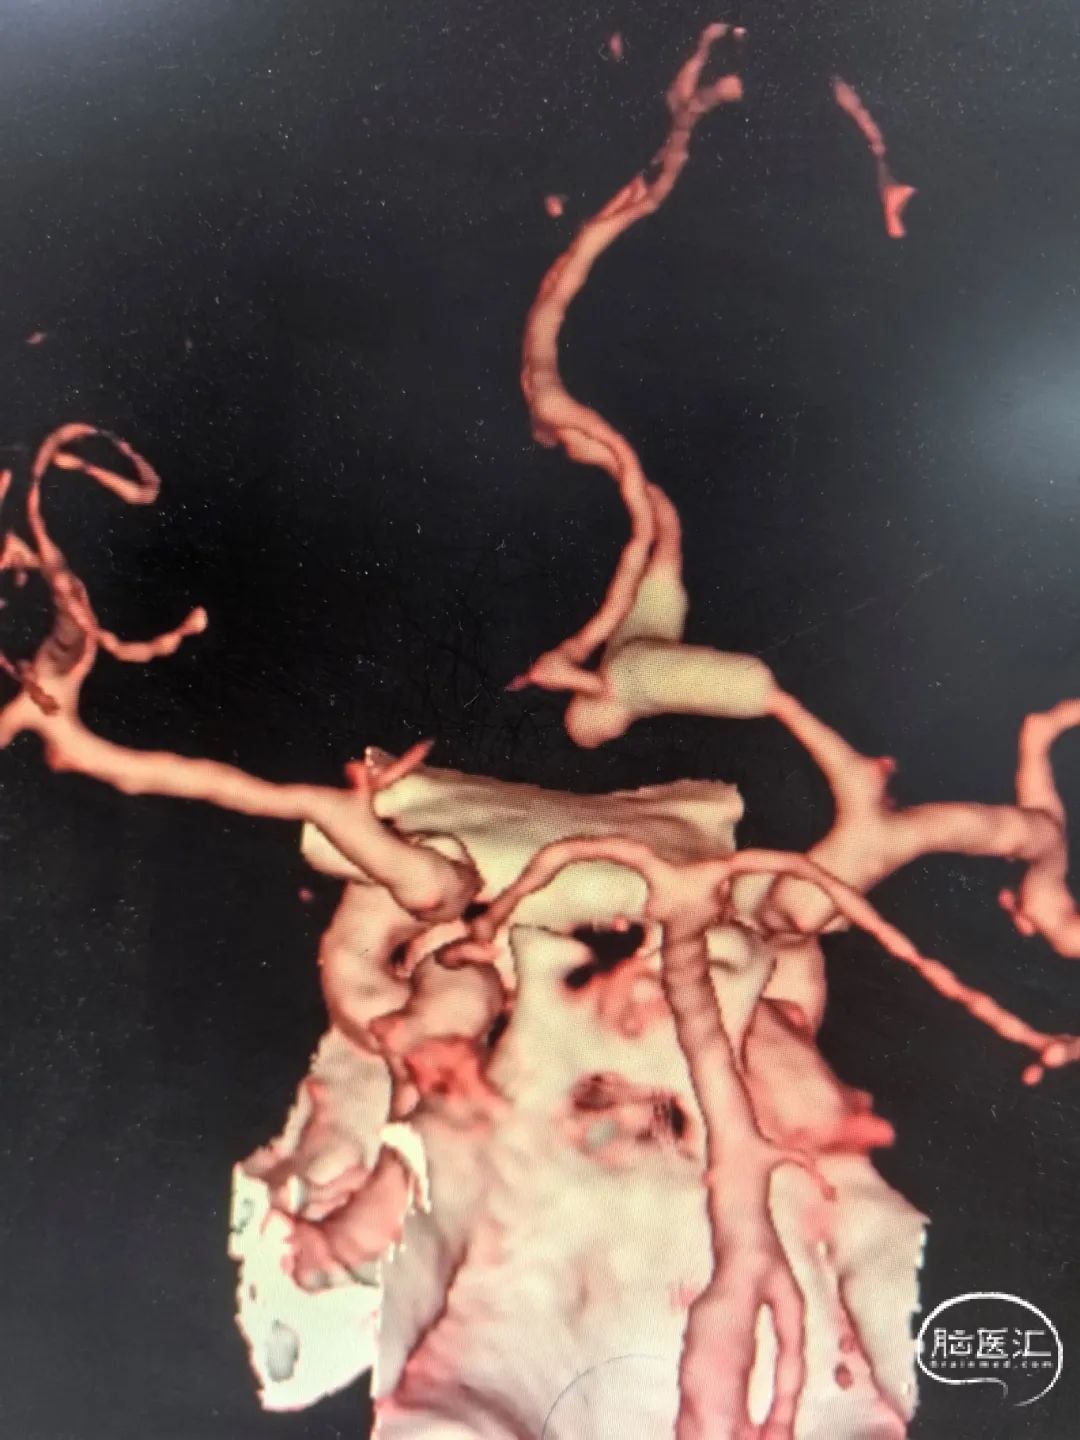

2025-1-19 DSA造影3D重建及方案讨论:

DSA造影3D重建测量

拟行脑动脉瘤密网支架置入术。

2.5mm*15mm Surpass Evolve密网支架,支架锚定区为右侧A2~A1